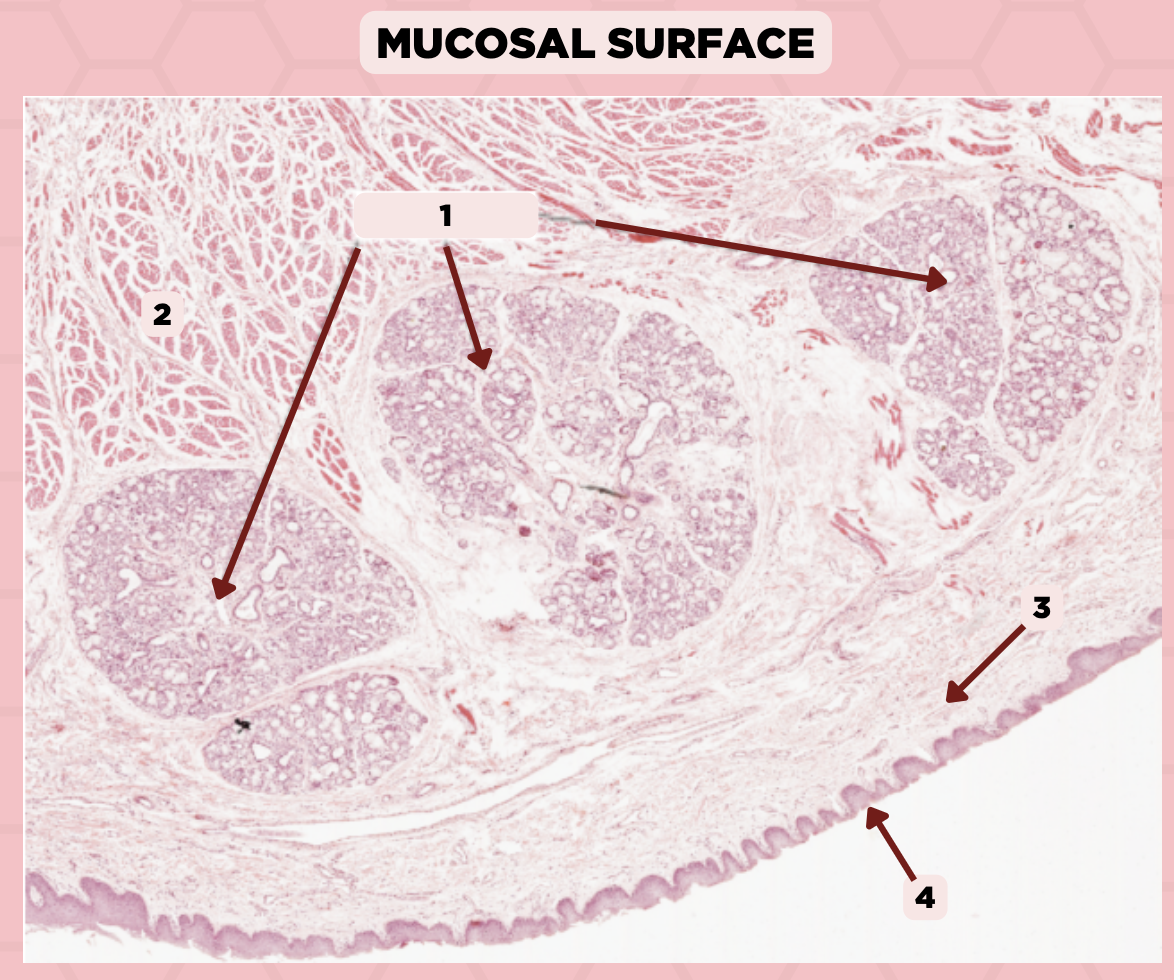

Lip

What specimen is showed in the picture?

Labial Glands (in the Mucosa)

Identify the structure labeled as 1.

Skeletal Muscle Cells

Identify the structure labeled as 2.

Lamina Propria

Identify the structure labeled as 3.

Mucosa

Identify the structure labeled as 4.

Lip

What specimen is showed in the picture?